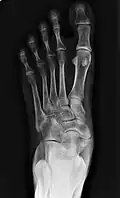

Images radiologiques

De gauche à droite : types 1, 2 et 3